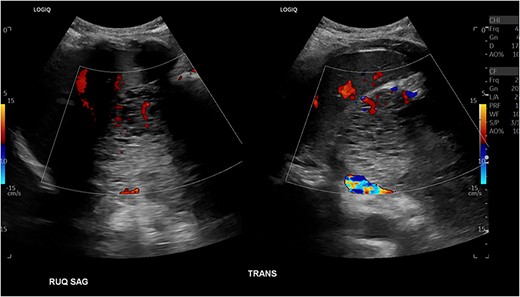

Patient presented one month later to the hospital from preadmission testing due to abnormal renal function. The patient endorsed dark urine, persistent unintentional weight loss, and decreased appetite with subsequent improvement of jaundice since PTC placement. She presented with abnormal serum biochemistry results: creatinine, 11.90 mg/dL [previously, 1.8 mg/dL] (normal range, 0.7–1.3 mg/dL); potassium, 2.9 mEq/L (normal range, 3.5–5.0 mEq/L); alkaline phosphatase, 142 U/L (normal range, 36–92 U/L); total bilirubin, 2.7 mg/dL (normal range, 0.3–1.2 mg/dL); direct bilirubin, 2.1 mg/dL (normal range, 0–0.3 mg/dL); aspartate aminotransferase (AST), 68 U/L (normal range, 0–35 U/L); alanine aminotransferase (ALT), 135 U/L (normal range, 0–35 U/L). Patient’s cancer antigen 19–9 was 2.2 U/mL (normal range, 0–37 U/mL). Abdominal ultrasonography showed a 13.0 × 9.4 × 8.3 cm mass in the right upper quadrant with numerous microcysts (Fig. 1).

Abdominal US showing a nonspecific mass in RUQ with numerous microcysts.